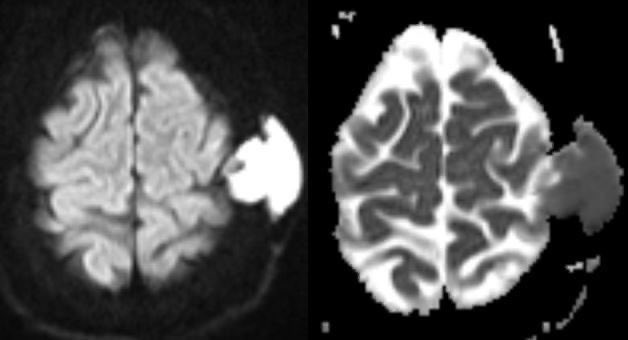

⭐️ What is the most likely diagnosis in this pregnant patient presenting with seizures? 🧠

#Neurology #medicine #radres #futureradres #Neurosurgery #MRI #FOAMed Image

Image

⭐️ Answer: Cortical vein thrombosis (CVT)

▶️CVT causes retrograde venous pressure leading to focal vasogenic edema

▶️Increased back pressure is characterized by dilated veins and petechial hemorrhage which can progress to large hematomas and ischemic neurological damage